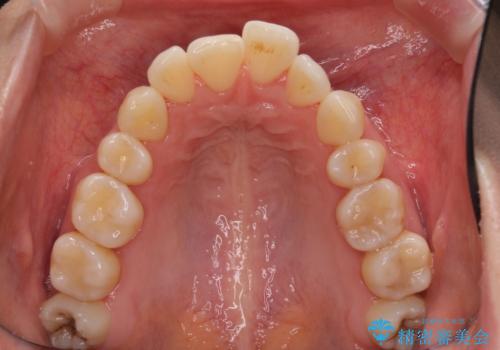

- 上の前歯の出っ歯を治したいとのことで来院された患者様です。

後戻りによる再矯正というもともあり、インビザラインを希望されていました。

上顎の歯は後方移動とIPR(歯と歯の間を削る)によって口元が引っ込むように、下顎は歯列全体の拡大とIPRによって上顎とバランスよく咬み合うように設計し、インビザラインにより治療を行うこととしました。

治療を開始して暫くして、勤務先から2年以上帰国することができず、それまでの移動がほとんど後戻りしてしまい、帰国後に再度後戻りをリカバリーするための治療を行うこととなりました。

5年以上の治療期間がかかりましたが、気になっている部分を改善することができました。